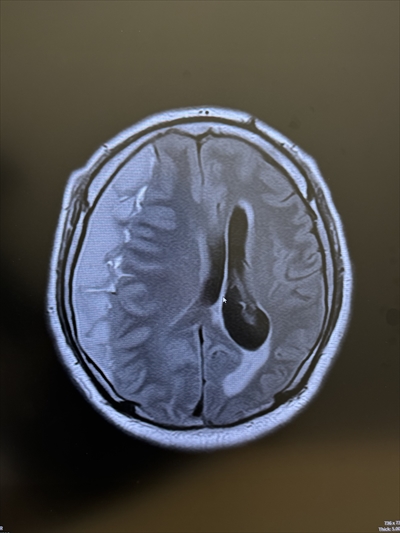

MRIの画像で、1/4に血が溜まり、脳を圧迫している状態だった。麻痺が出ており、予断を許さない命の危険もあった。